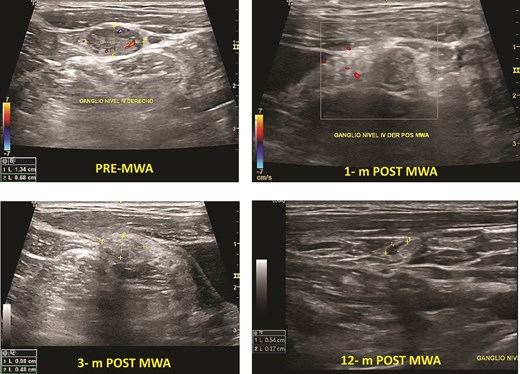

One patient had PTC. The mean baseline volume was 0.13 mm. After ablation, the mean volume at 1-month follow-up was 0.05 ml, and after 12 months, it disappeared. There was no local tumor progression or lymph node metastasis (Fig. 2).

Papillary thyroid microcarcinoma pre- and post-MWA (6 and 12 months). Note that the nodule’s vanishing, making it hard to identify it by ultrasound.